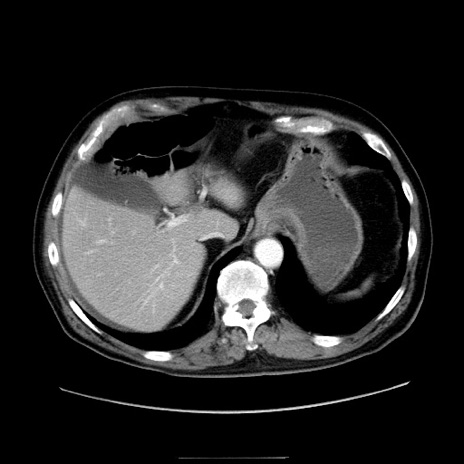

症例30(横断像)

【症例】80歳代男性

【主訴】臍周囲痛

【現病歴】約6時間前から臍下部痛が出現。次第に腹部膨隆・背部痛も生じてきたため来院。背部痛の場所は変化しない。

【既往歴】腎盂腎炎

【身体所見】意識清明、BT 36.3℃、BP  131/87mmHg、P 87bpm、SpO2 100%(RA)、臍周囲自発痛・圧痛あり、反跳痛なし、自発痛部位に一致して板状硬あり、腹部膨隆、腸雑音減弱、CVA tenderness両側陰性。

【データ】WBC 19600、CRP 0.33